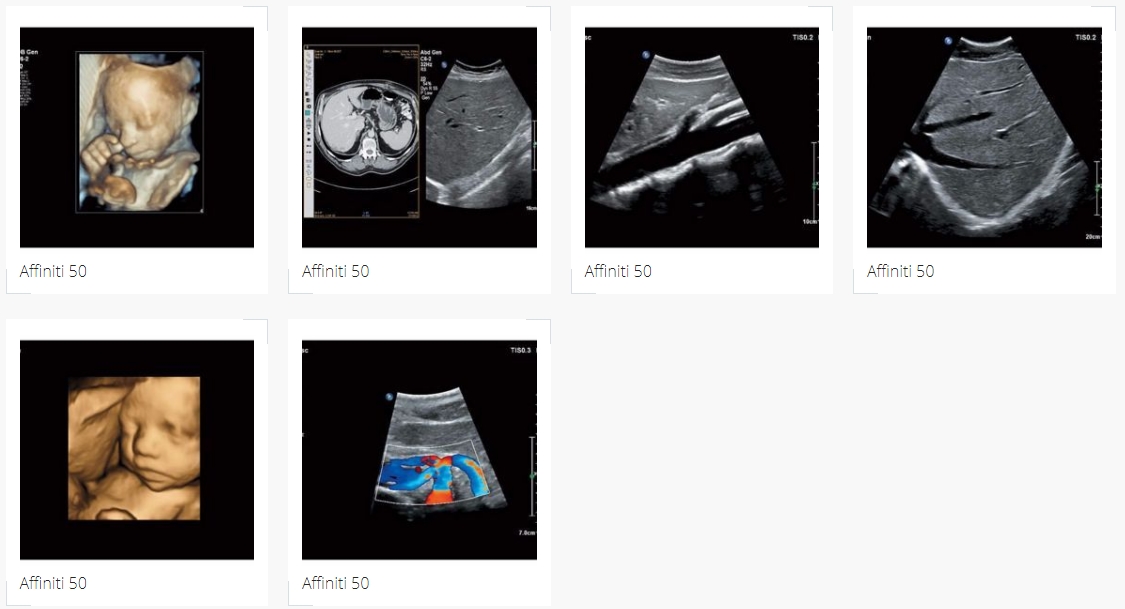

Это эффективный и надежный ультразвуковой аппарат, который обеспечивает качественную визуализацию даже при обследовании технически сложных пациентов.

При любых исследованиях Philips Affinity 50 обеспечивает превосходное качество визуализации, не требуя особых усилий для оптимизации изображений.

Он позволяет выполнять любые повседневные диагностические задачи и оснащен инновационными инструментами и средствами автоматизации, которые повышают эффективность исследований и упрощают рабочий процесс.

Эластография: Affinity 50 поддерживает компрессионную эластографию без внешней компрессии; этот высокочувствительный метод используется для оценки сравнительной жесткости тканей при исследовании разных органов, в том числе небольших поверхностных структур и молочных желез, а также в гинекологии.

Технология Anatomical Intelligence Ultrasound (AIUS) повышает эффективность повседневной работы. Такие инструменты AIUS как Automated Cardiac Motion QuantificationA.I. (aCMQA.I.) и Automated 2D Cardiac QuantificationA.I. (a2DQA.I.) позволяют оценить продольную деформацию миокарда (GLS) и фракцию выброса (EF) в двумерном режиме всего за десять секунд.

УЗИ с контрастным усилением: мгновенная оптимизация изображений с контрастным усилением и высокая результативность диагностики при использовании различных контрастных агентов дают возможность динамической оценки кровотока в органах и опухолях в реальном времени.